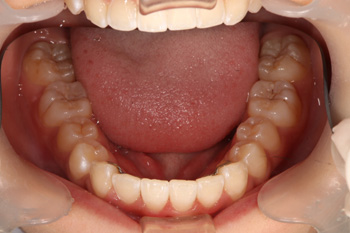

歯列育形成によるお子様の叢生の歯並び治療の症例

Before

装置は取り外しが可能な拡大装置という顎を広げる装置を使います。顎が広がった時点で、ブラケットにより歯並びの調節を行います。

小児矯正と成人矯正の違いは、歯を並べるスペースを拡げて作るか抜いて作るかというところがあります(※成人後も抜歯無しで並べれる場合もあります)。大人になってからの矯正では外科手術以外顎の骨格を変えることはできませんのが、Ⅰ期矯正を行うことで歯を並べるスペースを確保し、抜歯せずに歯を並べることが可能となります。約2年で、歯を並べるスペースを確保し、きっちり歯も並びました。

治療の内容 歯列育形成によるお子様の叢生の歯並び治療。

期間・回数 2年・23回(カウンセリング・検査含む)

費用 自由診療:歯列育形成 総額 580,000円(調整料36回分含む)税込701,800円